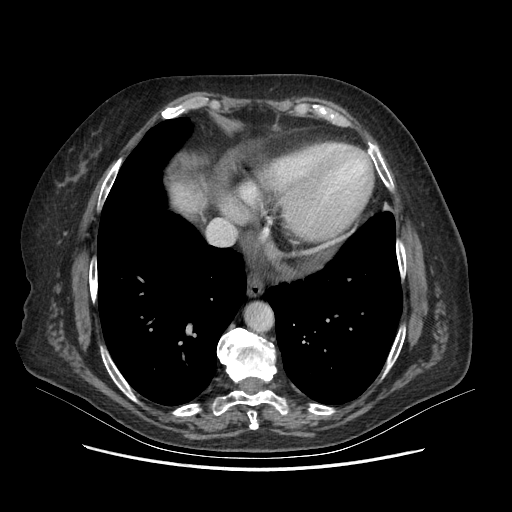

Targeted Slice 70 - Mediastinum Window Analysis (Generated vs Real Venous)

0.716

Mediastinum SSIM

38.6

Mediastinum RMSE

16.1

Mediastinum MAE

Average Mediastinum Window Metrics Across All Slices (101 slices) - Generated vs Real Venous

0.683

Mediastinum SSIM (Avg)

41.1

Mediastinum RMSE (Avg)

18.4

Mediastinum MAE (Avg)

Original VENOUS CT scan

Mediastinum window (WL 40, WW 400 β†’ Low βˆ’160, High +240)

Generated VENOUS CT scan (A→B translation)